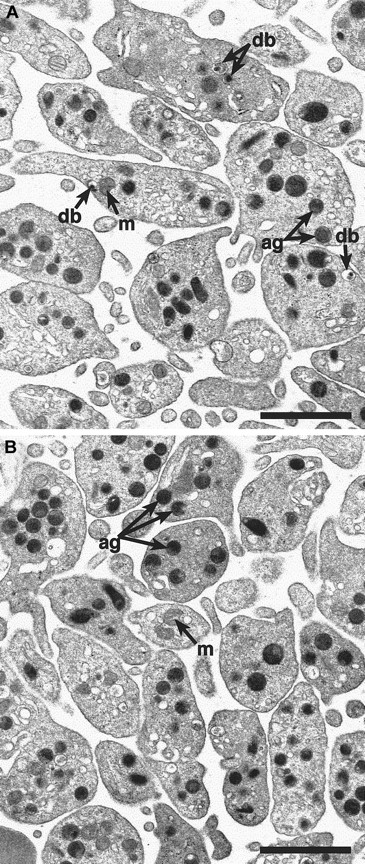

Alpha-granules appear normal in

cno/cno platelets. Transmission electron microscopy reveals a qualitatively normal structure and number of α-granules in cno/cno platelets. Representative photomicrographs showing normal (panel A) and cno/cno (B panel) platelets. m indicates mitochondria; db, dense bodies; ag, α-granules. Bar, 1 μm.

To determine if cno/cno mice have platelet SPD, we performed complete blood counts and measured bleeding times on adult mice. Despite normal blood cell counts, including platelets (Table1), bleeding times are markedly elevated, suggesting a qualitative platelet disorder (Table2). Electron microscopical examination of air-dried whole platelets reveals a dramatic decrease in visible dense bodies (Figure 2 A-B; Table 2); loss of dense body electron density suggests a low Ca++content.6 Similarly, platelet serotonin levels are decreased to approximately 3% of normal (Table 2). Collagen-induced platelet aggregation is significantly reduced, and ATP release is undetectable (Figure 2C). Hence, a profound deficiency of dense body contents characterizes homozygous cno platelets. Ultrastructurally, these platelets contain abundant α-granules whose size and number appear normal (Figure 3). The data are consistent with δ-SPD in cno/cnomice.